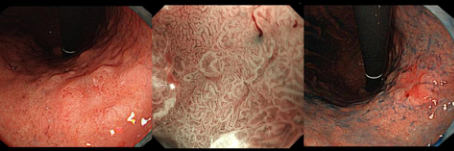

在科室何林方主任的带领下,科室常规开展无痛胃肠镜、精查染色胃肠镜、超声胃肠镜、色素放大内镜、窄带成像技术(NBI)、磁控胶囊胃镜、胶囊小肠镜等检查,能开展胰胆疾病的内镜下治疗(ERCP):包括十二指肠乳头肌切开(EST)、胆管取石术、胰胆管支架置入术、内镜下鼻胆管引流术;食管胃底静脉曲张套扎、硬化剂、组织胶注射治疗;内镜下的粘膜剥离术(ESD)、内镜黏膜下切除术(EMR)、经口内镜食管括约肌切开术(POME)、经内镜黏膜下隧道肿瘤切除术(STER)、空肠管置入术;痔硬化、套扎治疗;胃造瘘(PEG)、食管、肠道支架置入;食管狭窄扩张术,食管瘘口封堵术;经颈静脉肝内门-体分流术(TIPS)、超声内镜引导下的胃曲张静脉精准断流术(EUS-SVD)、内镜超声引导下胆道引流术(EUS-BD)、内镜下幽门括约肌切开术(G-POME)、经内镜逆行阑尾炎治疗术(ERAT)等国际最新内窥镜微创治疗。